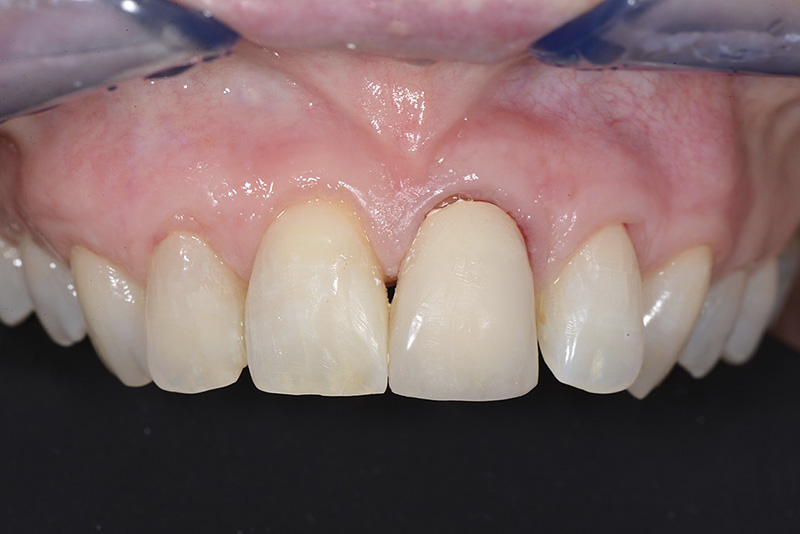

PREMESSA: in seguito all’estrazione dell’incisivo laterale superiore di destra, resasi necessaria per cause batteriche, si decide di affrontare il caso con il posizionamento di un impianto in sostituzione dell’elemento mancante dopo guarigione del sito infetto. Con tecniche rigenerative sia dei tessuti ossei mancanti a causa dell’infezione pregressa, sia dei tessuti gengivali che appaiono inizialmente troppo spostati in alto, si ripristina una corretta morfologia delle parabole (contorni) gengivali e delle papille interdentali (triangoli di gengiva tra due denti vicini).

Vengono utilizzati 2 tipi di provvisori: il primo, cementato ai denti vicini, viene utilizzato dal momento dell’estrazione del dente fino ad impianto osteointegrato (circa 6 mesi); il secondo, avvitato direttamente all’impianto, ha una funzione di prova estetica ma soprattutto di guida per la maturazione dei tessuti gengivali peri-implantari portandoli verso la maturazione completa prima di posizionare la corona finale in disilicato di litio.